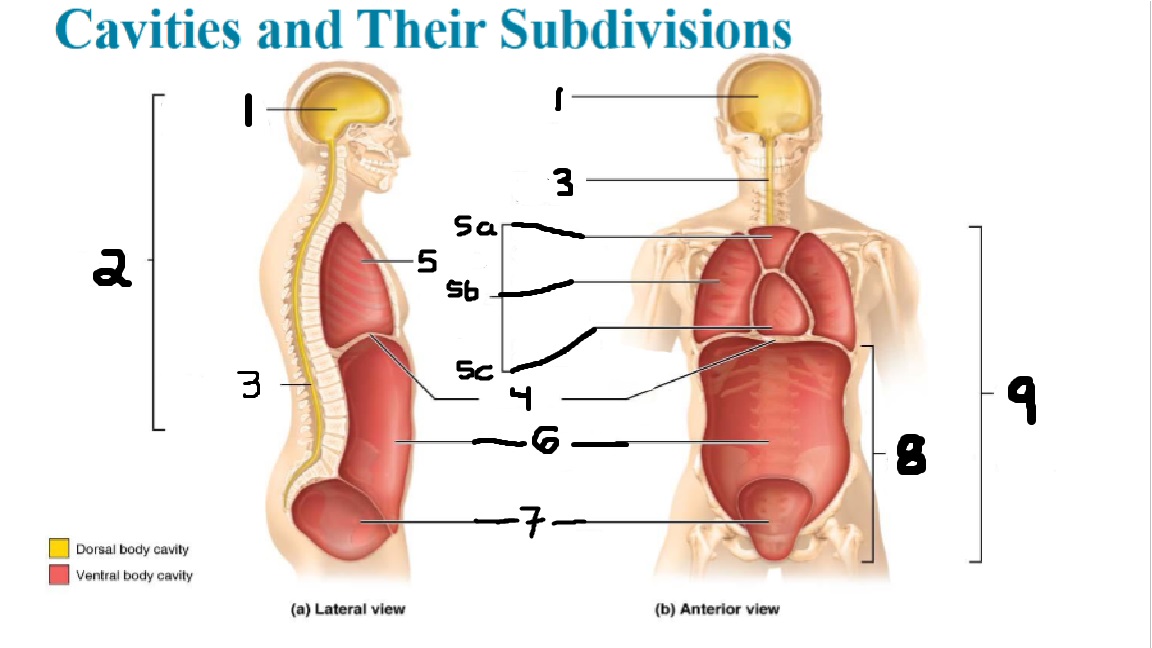

What cavities are part of the dorsal cavity?

The cranial and the Spinal (vertebral) cavities

What kind of cavity is labeled 2?

The dorsal body cavity (containing the cranial and spinal cavities)

What is the purpose of the dorsal cavity?

protects the nervous system

What is the main organ encased by the cranial cavity?

the brain

What cavity is labeled #1?

The cranial cavity

What is the main organ encased by the vertebral cavity?

the spinal cord

What is another word for the vertebral cavity?

the spinal cavity, or the spinal canal

What body cavity is labeled 3?

the vertebral cavity.

What cavities are included in the ventral cavity?

the thoracic, abdominal, and pelvic cavities.

What body cavity is labeled #6?

the abdominal cavity.

What are the main organs of the abdominal cavity?

the digestive organs such as the stomach, intestines, spleen and liver

What cavities are included in the Abdominopelvic cavity?

the abdominal cavity and the pelvic cavity

What body cavity is labeled #8?

The Abdominopelvic cavity

What does the diaphragm separate?

the thoracic and the abdominal cavities

What is labeled #4?

the diaphragm

What organs does the pelvic body cavity contain?

urinary/reproductive organs and rectum

What is labeled #7?

the pelvic cavity

What does the thoracic cavity encase?

the heart and the lungs

What is labeled #5?

the thoracic cavity

What part of the thoracic body cavity is labeled 5a?

superior mediastinum

What part of the thoracic body cavity is labeled 5b?

pleural cavity

What part of the thoracic body cavity is labeled 5c?

pericardial cavity within the mediastinum

What body cavity encloses the heart?

the pericardial cavity.